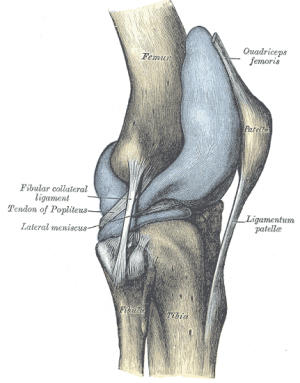

What is Patella Fracture Patella Dislocation

Patella Fractures

Patella Fractures Broken Kneecap of the Knee Knee Specialist

Patellar Fractures Physiopedia